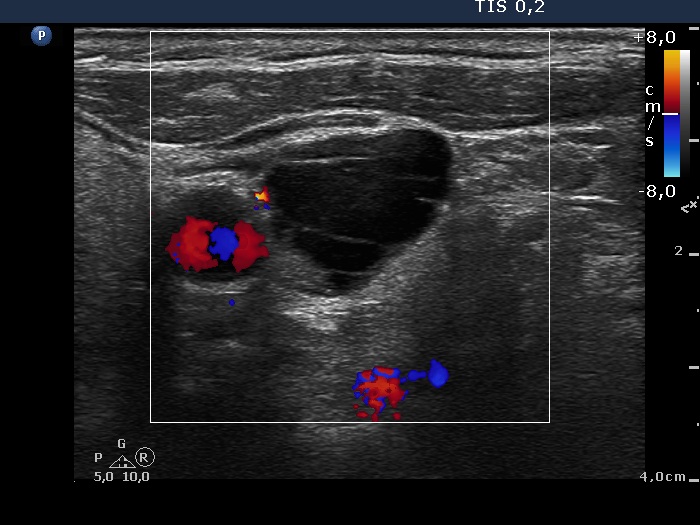

Left side of the neck, another transverse scan, color Doppler mode.